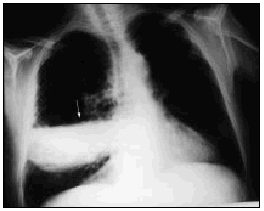

Varón de 60 años, diabético y con insuficiencia respiratoria crónica por enfisema pulmonar que ingresa por una neumonía en el lóbulo medio derecho. Se inició tratamiento con broncodilatadores inhalados, una cefalosporina de tercera generación y un macrólido, con mejoría inicial. En la tercera semana, ante la persistencia de cuadro febril, se realizó una radiografía de tórax (fig. 1) en la que se observa un infiltrado en el pulmón derecho de gran tamaño y con nivel hidroaéreo, por lo que se le añadió un antibiótico anaerobicida. En una TC torácica se observaba la lesión ya conocida (fig. 2. flecha izquierda) y otra pequeña imagen redondeada, con nivel hidroaéreo en su interior, en el espacio prevascular (fig. 2. flecha derecha). El fluido contenido en la lesión mayor era más denso que el agua y tenía burbujas de gas en su interior (fig. 2 punta de flecha). En un cultivo de esputo se cultivó Pseudomonas aeruginosa multisensible. Tras un acceso de tos, en una nueva radiografía de tórax (fig. 3) desaparece el infiltrado derecho, diseminándose la infección pulmonar, falleciendo el paciente días después en situación de shock séptico. Se estableció el siguiente diagnóstico: bullas pulmonares infectadas; bronconeumonía bilateral por P. aeruginosa.

Fig. 2.